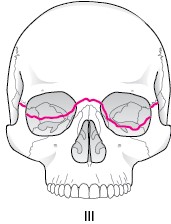

LefortV型骨折

鼻骨を横断し、眼窩後壁を経て下眼窩裂、頬骨の前頭突起を通り後方へ向かい、上顎骨と蝶形骨の間を通過する

骨折です。

顔面骨が頭蓋底と分離します。

眼窩下神経(頬部・上唇の知覚鈍麻(脱失))、眼窩損傷、鼻出血、などを生じます。